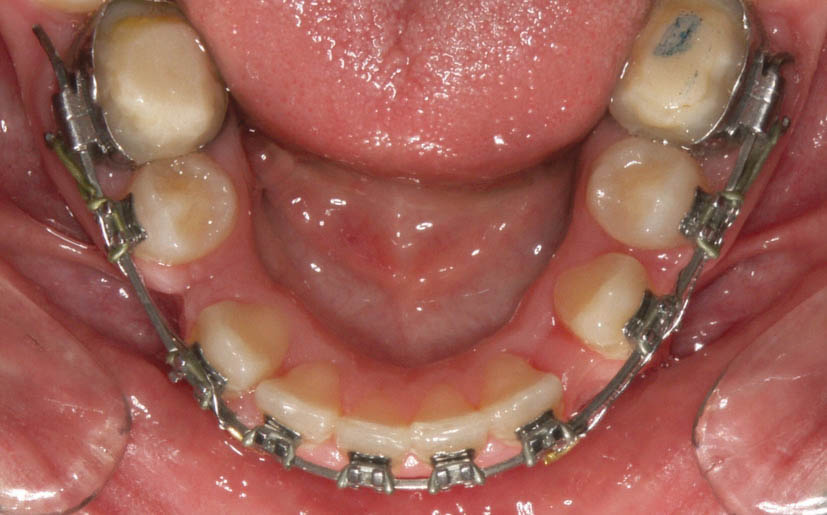

نوع باز آن به نام open coil spring برای باز کردن فضا استفاده میشود. مثلاً دندان لترال در کراس بایت است (شکل 184-1) و فضا برای قرار گیری درون قوس فکی ندارد.

شکل 184-1: وقتی فضا برای درون قوس قرارگرفتن لترال پالاتالی نداریم از فنر open نیتی استفاده میشود تا فضا باز شود.